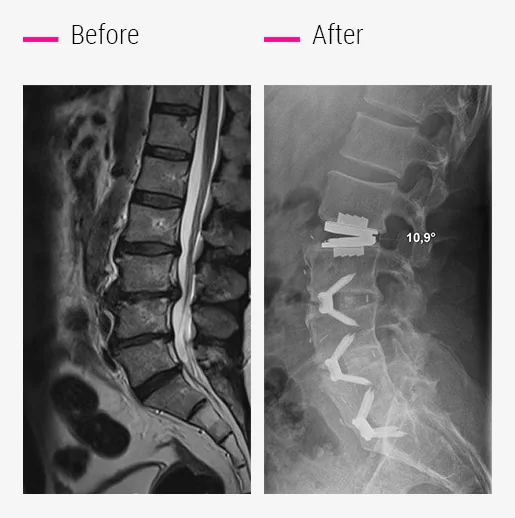

in the event of damage to multiple discs?

Up to 4 lumbar discs can be replaced in a single surgery.

Depending on the degree of wear, each disc will be replaced with either a mobile or a fixed implant.